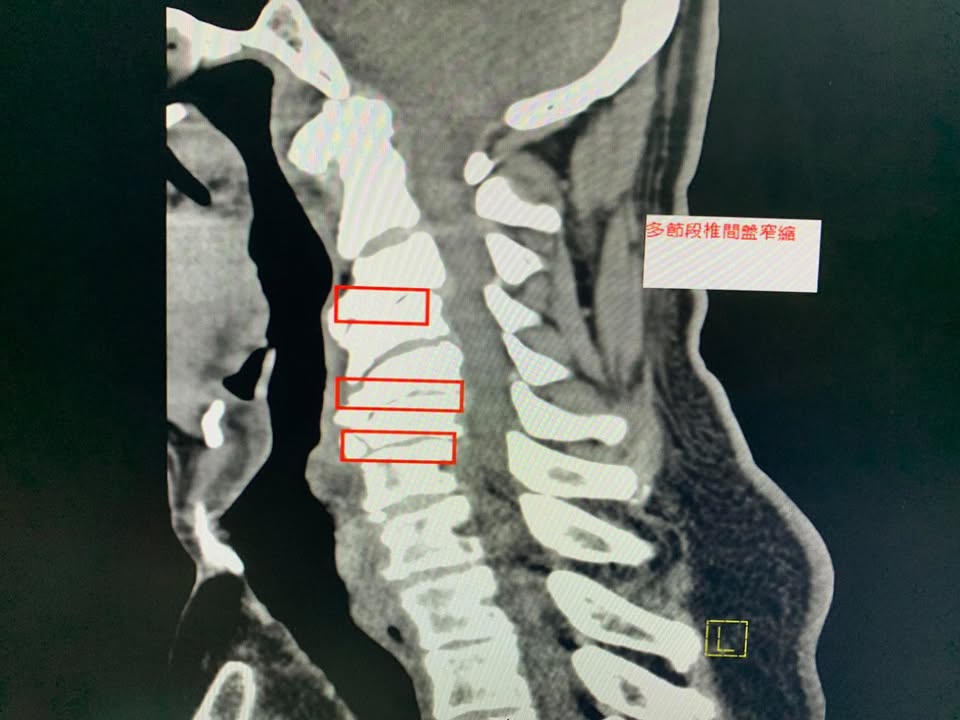

😂😂來自印尼的高先生抱怨右側肩膀非常刺痛且上臂無力與麻痛,原因是幼年的一場嚴重車禍,導致整個骨骼變形,多年來肩頸長期痠痛,一直到最近這一兩年嚴重惡化,這中間做過傳統整復,有改善但是很容易發作,今年四月在台北榮總拍攝x光片與電腦斷層CT,發現頸椎變形嚴重與椎間隙嚴重狹窄合併神經根卡壓,神外醫師建議開刀裝設人工椎間盤,但是患者畏懼開刀,經過友人介紹來接受頸椎中醫微創療法,說實在的,這是一個難度非常高的案例,多節椎間盤坍塌,椎體骨刺增生非常嚴重,頸椎弧度完全消失還變成反弓!這樣的片子看得心驚膽顫,患者抱怨右手開始變得沒力而且很容易麻痛,頭向後仰就開始疼痛,觸診頸椎肌肉跟關節面都非常緊,裡面條索筋結非常多

椎間盤突出,相鄰椎體後緣及外側緣的骨刺形成,小關節及鉤椎關節的增生肥大,黃韌帶的增厚及向椎管內形成皺摺。都可能刺激或壓迫椎管兩旁的頸神經根,引起上肢包括手指的疼痛、麻木和肌力減退等症狀

事實上椎間盤在二十歲就發生退行性病變,大部分的人都是正常退化,但現代人手機電腦不離身,低頭族當久了,頸椎的生理曲線消失,變成頸椎過直,之後慢慢使得椎間盤的髓核突出,然後開始刺激與壓迫神經根,進一步產生周圍軟組織水腫發炎,最後產生纖維組織嚴重沾黏跟微循環障礙